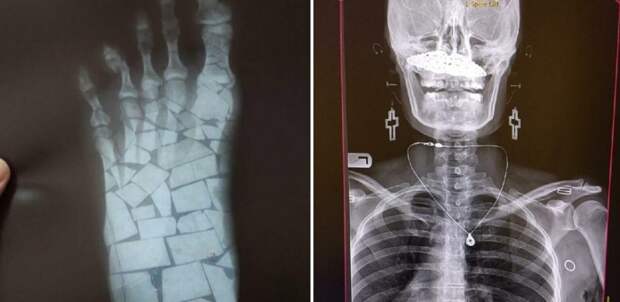

На форуме для врачей-радиологов Radiopaedia помимо серьезных материалов публикуют и необычные рентгеновские снимки, вроде здоровенной банки в заднем проходе и прочих «сокровищ». Давайте и мы посмотрим на интересные снимки, разобраться в которых удается не сразу.